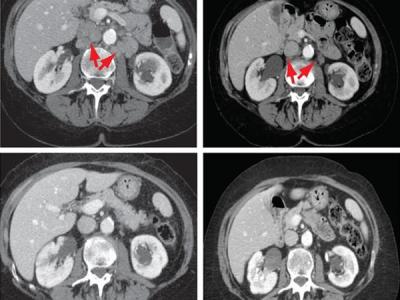

落选癌症药物对部分人群有效

这个膀胱癌患者的转移瘤在服用了一种试验药物后消失了 大多数试验性癌症药物根本...